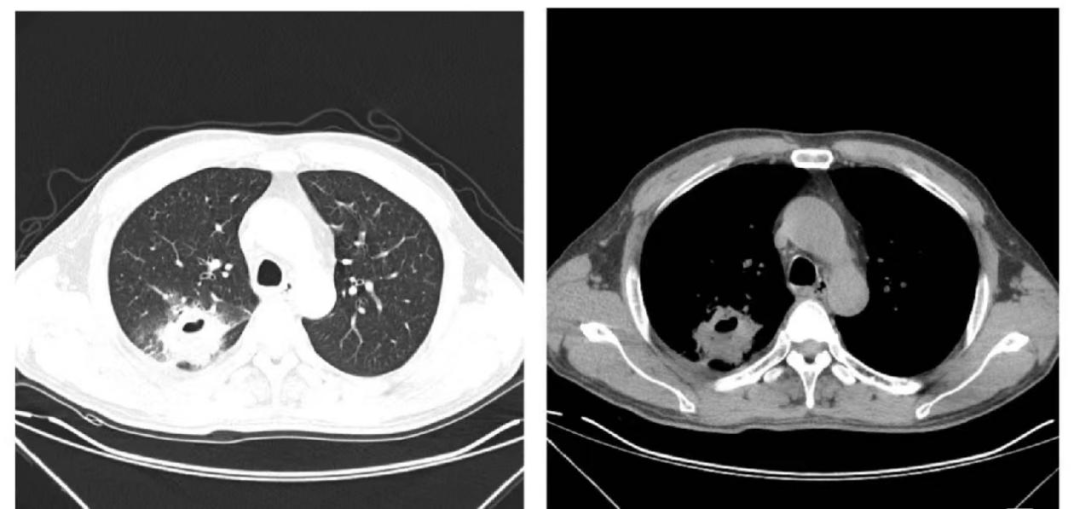

(CT断层扫描发现病灶)

CT 检查把人体结构扫描成多层的断面图像,即横断剖面图,组织之间互不重叠干扰,其中薄层扫描可发现2mm以上的肺结节,图像更清晰,这是 DR 不能实现的,但辐射剂量较胸片大,费用昂贵。